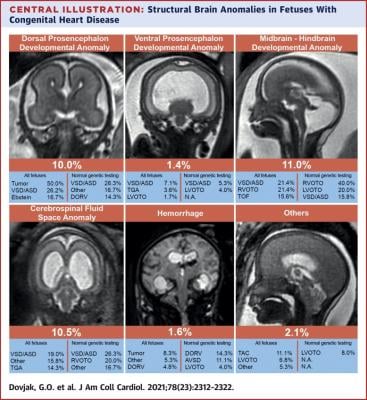

Heart defects are among the most common congenital abnormalities and affect almost 1% of all newborns. Early and comprehensive evaluation of fetuses with sonographically diagnosed heart defects using fetal Magnetic Resonance Imaging (MRI) as well as other techniques is important for the care of the child with a heart defect and the diagnosis of possible further abnormalities, both before and after birth. A new study conducted by the Department of Biomedical Imaging and Image-guided Therapy in collaboration with the Division of Obstetrics and Feto-Maternal Medicine within the Department of Obstetrics and Gynecology of MedUni Vienna and University Hospital Vienna shows that almost 57% of fetuses with heart defects also had at least one other abnormality on the MRI, and approximately a quarter of all fetuses had structural brain abnormalities. According to the study, the severity of the heart defect has no influence on the rate of extracardiac abnormalities in other organs. The study looked at 442 fetuses with heart defects between the 17th and 38th week of gestation.

Fetal MRI can be used to obtain high-resolution images of the fetal organs, irrespective of the mother's body weight or the amount of amniotic fluid present. This reliable prenatal imaging allows abnormalities to be identified and further treatment steps to be initiated at an early stage. A particular strength of fetal MRI is accurate assessment of structural brain abnormalities that are sometimes difficult to detect using ultrasound. One of the major fetal MRI centres in Europe is located within the Department of Biomedical Imaging and Image-guided Therapy, where several fetal MRI scans are performed on a daily basis.